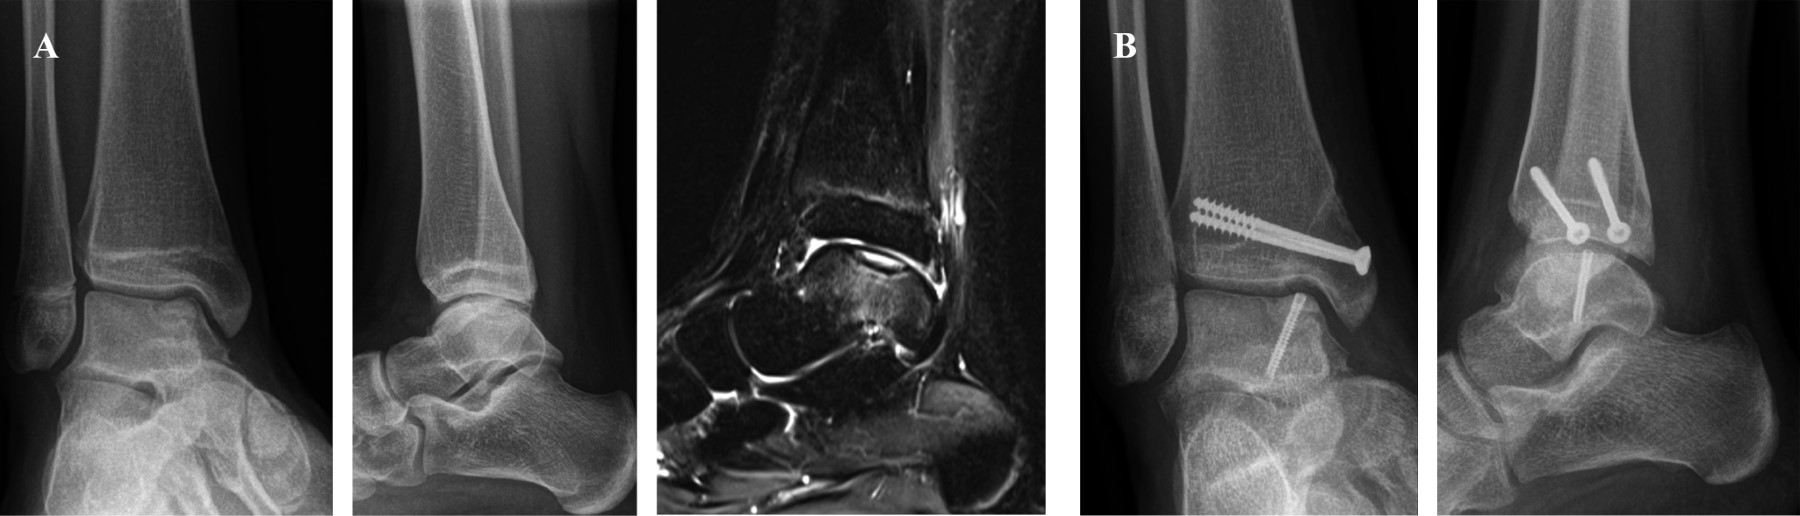

Figura 3